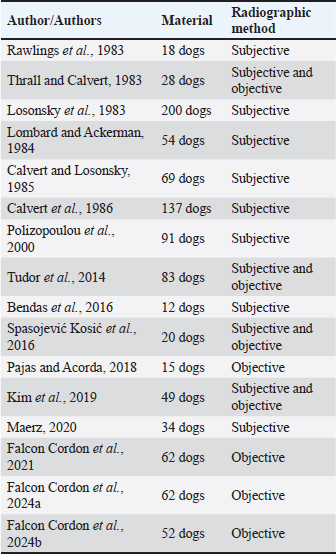

AbstractBackground: Heartworm disease (HWD) represents the pathological consequences of heartworm (HW) (Dirofilaria immitis) infection on different organs and organ systems, primarily the lungs and heart. Radiography can objectively assess the severity of cardiopulmonary disease secondary to HW infection. However, interpreting dogs’ radiographs can be quite challenging with respect to choosing an appropriate radiographic method. Aim: The aim of this article is to review the published literature on radiographic methods, both subjective and objective, emphasizing their advantages and disadvantages. In order to define the feasibility and findings of the used radiographic methods, radiographs (laterolateral-LL and dorsoventral-DV) of dogs (N=40) naturally infected with HWD were retrospectively analysed. Methods: Subjective radiographic assessment included all parameters of abnormal lung patterns and right-sided cardiomegaly in HWD. Objective methods used for the assessment of cardiac size and shape were: modified vertebral heart size (modified VHS), manubrium heart score, sternebral heart size (SHS), thoracic inlet heart size, and cardiac sphericity index (CSI). Blood vessels were measured and expressed in relation to different skeletal structures or the aorta, depending on the blood vessels. Results: While the increased sternal contact, reversed D heart shape, and loss of pulmonary vessel margination were the most feasible subjective parameters, the modified VHS, SHS, and CSI (VHS-LL=10.52 ± 0.97, VHS-DV=10.79 ± 1.12; SHS-LL=9.22 ± 1.04; SHS-DV=9.49 ± 0.96; CSI-LL=0.86 ± 0.08, CSI-DV=0.75 ± 0.07) were the most feasible objective methods. The ratios of the right cranial lobar artery (RCrLA) to the fourth thoracic vertebra (T4) and the fourth rib (4.r) were the most feasible blood vessel measurements (RCrLA/T4=0.27 ± 0.08, RCrLA/4.r=0.89 ± 0.25). In 5% of the dogs, radiographs could only be assessed subjectively. The most prevalent subjective parameters were increased sternal cardiac contact (91.89%), reversed D heart shape (89.65%), RCaLA enlargement (86.67%), and loss of pulmonary vessel margination (84.21%). The main pulmonary artery enlargement in LL, and the areas of increased opacity that tend to coalesce, significantly changed after successful HWD therapy. Conclusion: The most feasible and prevalent subjective parameters were the increased sternal contact, reversed D heart shape, and loss of pulmonary vessel margination. The most feasible objective methods were the modified VHS, SHS, and CSI. Keywords: Heartworm disease, Radiographic methods, Dogs. IntroductionHeartworm disease (HWD) implies heartworm (HW) infection, but also goes beyond this term. Diagnosis of HWD consists of the HW infection detection, and the determination of pathological consequences on relevant organs and organ systems (primarily on the lungs and heart, but also on the kidneys, joints, blood, and immune system) caused by a parasite—HW (Dirofilaria immitis—D. immitis). While the detection of HW infection is based on identifying circulating microfilariae and adult parasite antigen in blood samples, the diagnosis of HWD can require different diagnostic methods depending on the compromised organs or organ systems. The pathological consequences on different organs and organ systems are a result of the pathogenesis of the HWD. Since the parasite resides in the pulmonary arteries, the initial pathological lesion is villous myointimal proliferation (endothelial cell swelling, widening of intracellular junctions, increased endothelial permeability, and periarterial oedema). Endothelial damage further leads to arterial thrombosis, while endothelial permeability and periarterial oedema result in pulmonary infiltrates (neutrophils and eosinophils) and lung consolidation. Pulmonary eosinophilic infiltrates in HWD (eosinophilic bronchopneumopathy, allergic pneumonitis) are considered to be a manifestation of immunologic hypersensitivity caused by the HW (Knight, 1980; Schaub et al., 1981; Keith et al., 1983; Kittleson, 1998; Ware, 2011). When inflammatory pulmonary changes become chronic, their end-stage can be lung fibrosis (Kittleson, 1998). After the parasites die (either naturally or therapeutically), a more intensive host reaction, such as pulmonary thromboembolism (PTE), severe lung tissue damage, shock, and coagulopathy occurs (Kitoh et al., 1994a,b; Kitoh et al., 2001). In addition, severe complications of the HWD may include pulmonary hypertension (PH), right-sided heart failure and caval syndrome. HWD-induced PH is a consequence of increased pulmonary vascular resistance caused by intimal and media thickening of the pulmonary arteries and an obstruction of blood flow in the pulmonary arteries. The aforementioned vascular changes increase the right heart afterload, causing right ventricular hypertrophy and cor pulmonale (Dunn, 2000). Caval syndrome is a severe complication of the HWD, caused by the obstruction of v. cava caudalis (VCC) due to large-scale parasite infestation and their aberrant location towards the right heart (Atkins et al., 1988; Jones, 2016). Besides cardiovascular and pulmonary changes, microfilariae act as circulating antigens in blood, and thus have the potential to stimulate an immunological reaction and form immune complexes, with immune complex depositions in glomeruli or synovial membranes, causing glomerulonephritis or reactive polyarthritis (Dunn, 2000). The complex pathogenesis of the HWD and its pathological changes can be registered by the use of different diagnostic methods. In this article, we will focus on cardiopulmonary manifestations of the HWD, which are by far the most common in clinical practice. Radiography is considered the most objective method of assessing the severity of cardiopulmonary disease secondary to HW infection (AHS, 2025). The aim of the study is to review the literature on the subject of radiographic methods and their features relevant to the HWD, and to retrospectively analyze the feasibility and results of these methods in radiographs of dogs naturally infected with HWD. Literature reviewThoracic radiography is performed in dogs with HWD in order to see the morphology of the lung field and cardiac silhouette, and thus to determine respiratory and cardiovascular pathological changes caused by the parasite. Radiographic changes associated with HWD can be assessed both subjectively and objectively (Table 1). While subjective assessment of radiographs identifies and describes the presence of pulmonary vascular, parenchymal, and interstitial changes, as well as cardiac size and shape, objective radiographic assessment measures and determines cardiac size and shape, as well as the size of blood vessels relevant for HWD. Subjective radiographic assessment shows greater interobserver variability in comparison with objective methods, which are considered to be more reliable for inexperienced veterinarians as well as in questionable cases (Buchanan and Bücheler, 1995; Lamb et al., 2000; Hansson et al., 2005). Table 1. References selected on the basis of radiographic assessment in HW-infected dogs.

Typical vascular abnormalities include a bulging pulmonary artery segment and enlarged lobar pulmonary arteries, with peripheral pulmonary arteries becoming tortuous and truncated (Ackerman, 1987; Kittleson, 1998; Dunn, 2000; Polizopoulou et al., 2000). Arteritis lies at the root of enlarged arteries, to which PH may also contribute. Severe arteritis produces pulmonary artery tortuosity (Kittleson, 1998). Dead parasites act as pulmonary emboli, interrupting blood flow to lung segments, leading to the appearance of suddenly terminated pulmonary arteries, seen as blunted or pruned arteries (Kittleson, 1998). The enlargement of lobar pulmonary arteries, without concurrent venous distension, is strongly suggestive of HWD or other causes of PH (Ware, 2011). The right caudal lobar artery (RCaLA) is most commonly and heavily infested due to the effect of blood streaming toward this artery. Following the RCaLA, the left caudal lobar artery and subsequently, the cranial lobar arteries are the next commonly affected (Kittleson, 1998). Normally on radiographs, the VCC emerges through the diaphragm and slopes slightly cranioventrally towards cardiac caudal margin. It is similar in size to the aorta (Ao), but may get wider towards the heart (Herrtage and Denis, 1997). Enlargement of the VCC has been reported as a radiographic finding of right-sided cardiomegaly (Suter and Lord, 1984). Pulmonary parenchymal abnormalities vary from increased lung densities, seen in dogs with mild-moderate disease, up to generalized densities throughout the lung field (Kittleson, 1998). Parenchymal abnormalities, apparent especially after adulticide therapy, are seen as patchy alveolar densities (Dunn, 2000). Patchy pulmonary alveolar or interstitial infiltrates are the result of oedema, pneumonia, infarction, or fibrosis. Pulmonary opacities may be perivascular (Ware, 2011). Concerning heart remodeling, right ventricular enlargement is a characteristic radiographic feature (Dunn, 2000). This is a secondary change, arising as a consequence of PH. Right heart enlargement is seen in dogs with moderate to severe PH, and is best assessed on either the dorsoventral (DV) or ventrodorsal (VD) radiographic view (Lombard and Ackerman, 1984). Objective radiographic methods in HWD assess overall cardiac size and shape, and the size of blood vessels relevant to HWD in relation to various skeletal structures (intercostal spaces, vertebrae, sternebrae, thoracic inlet (TI), and etc.). The intercostal space method is based on counting the number of intercostal spaces that cover the heart silhouette (Buchanan, 1968; Buchanan and Bücheler, 1995). Although introduced a long time ago, it is still used, and like all other methods has its advantages and disadvantages. It is well known among clinicians and easy to use, because it is directly performed by counting the number of intercostal spaces while observing a dog’s lateral radiograph (LL). A normal heart silhouette has the size of 2.5 to 3.5 intercostal spaces, for deep-chested or wide-chested dogs respectively (Buchanan, 1968; Kealy, 1979; Owens, 1985). However, false negative and positive findings are possible due to thorax conformation, the position of the heart in the thorax, phase of respiration and position of the diaphragm, superimposition of ribs, and imprecise reference points (Buchanan and Bücheler, 1995). In 1995, the vertebral heart size (VHS) was introduced as an objective method, which expresses heart size through long axis (LA) and short axis (SA) normalized to the midthoracic vertebrae, starting from the fourth thoracic vertebra (T4) (Buchanan and Bücheler, 1995). In LL of dogs, the reference point for the cardiac LA is the ventral border of the left mainstem bronchus and the most distant ventral contour of the cardiac apex. This length reflects the combined size of the left atrium and left ventricle. The measured cardiac LA, made by using an adjustable caliper, is then repositioned over thoracic vertebrae beginning with the cranial edge of the T4. The distance to the caudal caliper point is then estimated to the nearest 0.1 vertebra (v). The maximal cardiac SA is measured in the central third region, perpendicular to the cardiac LA axis, and then also repositioned along thoracic vertebrae starting from the beginning of T4. The sum of LA and SA dimensions represent the overall size of the heart expressed as total units of vertebral length to the nearest 0.1 v. In DV or VD radiographs, the maximum LA and SA of the heart are determined with calipers in a similar fashion and measured against vertebrae in the LL radiograph beginning with T4 (Buchanan and Bücheler, 1995; Buchanan, 2000). The determined VHS in normal dogs is 9.7 ± 0.5 v in LL radiographs, and 10.2 ± 1.45 and 10.2 ± 0.83 v in DV and VD, respectively (Buchanan 2000). By using this method many studies have proposed breed-specific VHS reference values (Lamb et al., 2001; Gulanber et al., 2005; Bavegems et al., 2005; Marin et al., 2007; Castro et al., 2011; Jepsen-Grant et al., 2013). The following factors were found to influence mean VHS: interbreed variations, interobserver differences concerning references points of LA and SA, transformation into vertebral unit (v), and anomalies of thoracic vertebrae and intervertebral disc diseases (Hansson et al., 2005; Jepsen-Grant et al., 2013), cardiac cycle and, to a lesser extent, respiratory cycle (Olive et al., 2015). In order to overcome some of these limitations, modifications of this method, concerning the determination of reference points for SA of the heart and the introduction of the VHS unit (the length of one thoracic vertebra), have been proposed (Hansson et al., 2005; Spasojević Kosić et al., 2007; Costanza et al., 2022). The manubrium heart score (MHS) is proposed as the method that can overcome some limitations of the VHS method (Mostafa and Berry, 2017). In this method, the length of the manubrium (M) is used as a reference value to normalize the measurement of the height and width of the cardiac silhouette in right LL and VD thoracic radiographic views. On the LL view, the cardiac LA is measured from the ventral border of the carina to the caudoventral margin of the cardiac apex. The cardiac SA is measured on a line perpendicular to the LA at the widest point of the cardiac silhouette. On the VD view, the cardiac LA is measured from the distance of the right cranial margin of the heart silhouette to the cardiac apex, and the SA heart axis is measured at the widest line perpendicular to the LA. The M length is measured as the maximum M length on the right LL view. The reason why the M of the sternum is selected is that it is relatively prominent, easily identified, and measured on LL radiographs. At the same time, an evenly elongated, bullet-shaped, rectangular, or camel head-neck-shaped M is accepted for the MHS measurement. However, if the M of dogs is abnormal or its cranial edge cannot be identified, the calculation of the MHS is not possible. Established values of the MHS in normal healthy dogs vary from 4.8 ± 0.5 to 5.3 ± 0.8 in LL view, and from 5.4 ± 0.6 to 5.8 ± 0.9 in VD view in large and small dogs, respectively (Mostafa and Berry, 2017). Furthermore, the MHS is recommended as a useful, objective method for heart disease screening in dogs, capable of distinguishing between left-sided and right-sided cardiomegaly (Mostafa et al., 2020). In addition to MHS, the cardiac sphericity index (CSI) is another measure of the shape of the heart, which can be used to assess the globe-shaped heart. It is calculated by dividing the cardiac SA by the cardiac LA. The value of CSI≥1.00 means a near round figure of the cardiac silhouette (Guglielmini et al., 2012). Recently, the sternebral heart scale was proposed for the assessment of heart size in ferrets (Gutiérrez et al., 2022). Upon determination of cardiac LA and SA in radiograph views, the LA and SA of the heart are measured along the sternum, starting at the cranial edge of the fourth sternebra (S4). The sum of the cardiac LA and SA is expressed in sternebral units (s), estimated to an accuracy of 0.1 seconds. Thus, it determines the sternebral heart size (SHS) in this species. This method overcomes the limitation of the MHS caused by the abnormal shape of the M or the impossibility of cranial margin M line identification (Gutiérrez et al., 2022). Although the correlation between heart size and sternebral length was slightly lower compared to the correlation with the vertebral length in dogs (Buchanan and Bücheler, 1995), to the best of our knowledge, no study on the subject of the normal SHS in dogs has been published yet. First proposed as a reference point to assess tracheal diameter in brachycephalic and non-brachycephalic dogs (Harvey and Fink, 1982; Mostafa and Berry, 2022), the TI has recently been assessed as a unit for measuring thoracic inlet heart size (TIHS) (Marbella Fernández et al., 2023a). In this study, the TIHS has proved to be a simple and accurate method for measuring heart size, which overcomes some limitations seen in previously mentioned methods, such as vertebral or M malformations, and variations due to dog’s size and breed. Reference points for the cardiac LA and SA in this method are like the ones described for the VHS. Upon being measured the cardiac LA and SA are summed and divided by the corresponding TI length. The TI, defined as the minimum length of the TI, is determined as the distance between the cranio-ventral aspect of the first thoracic vertebra and the cranio-dorsal margin of the M at its highest point. The mean TIHS value for normal dogs is 2.86, and a TIHS value above 3.2 is considered to be an increased heart size in dogs (Marbella Fernández et al., 2023a). Besides methods based on linear determination of cardiac size through its LA and SA, which are then expressed by different skeletal structures, methods based on the estimation of cardiac areas have also been investigated. One of these modalities for cardiac size evaluation is the ratio between cardiac and thoracic areas (Torad and Hassan, 2014). Determination of the cardiothoracic ratio derived from LL thoracic radiographs (Empel and W, 1974) or on both LL and VD radiographs after peak inspiration and expiration (Castro et al., 2011; Torad and Hassan, 2014). Another way of assessing heart size is to compare the heart area to the T4 body area (So et al., 2024). These methods showed not only a correlation with VHS (Azevedo et al., 2016; So et al., 2024), but also, and to a higher extent, with the cardiac volume measured by computed tomography (So et al., 2024). However, these methods are complicated and require specific software, not always available in clinical practice. In addition, thoracic cavity conformation varies in different dog breeds, and individual changes in healthy and diseased animals (Buchanan and Bücheler, 1995; Castro et al., 2011; Torad and Hassan, 2014) make these methods of limited use. Blood vessels relevant to HWD (RCrLA, RCaLA, VCC) can also be assessed objectively, by comparing them with different skeletal structure, or, in case of the VCC, with the Ao. The width of the RCrLA on a LL view in normal dogs should not exceed the narrowest diameter of the 4th rib (4.r). On DV radiographs, the width of the RCaLA is normally not larger than the 9th rib (9.r) at the level of their intersection (Herrtage and Denis, 1997; Ware, 2011). Furthermore, ratios of RCrLA/4.r≥ 1.08, and RCaLA/9.r≥ 1.10 indicate the presence of PH, and thus show potential as a preliminary screening tool for PH in HW-infected dogs (Falcon Cordon 2024a). The measurement of VCC size and its ratio towards other fixed-sized surrounding structures, such as the length of vertebrae at the level of tracheal bifurcation, the descending Ao, and the width of the 4.r can help in the detection of right-side heart disease in dogs (Arya et al., 2021). The diameter of VCC should be considered normal in a dog with a ratio of VCC/Ao < 1.00, VCC/ v < 0.80, or VCC/4.r < 2.25 (Lehmkuhl et al., 1997). Material and MethodsData used in this study related to client-owned dogs in which HW infection was identified. For this purpose, the medical records of these dogs were reviewed with the collection of all data relevant for the retrospective radiographic analyses. The material for this study included radiographs of 40 dogs naturally infected with D. immitis. There were two criteria for this study. The first one was a complete HW infection diagnosis performed in these dogs (detection of antigen of adult parasite D. immitis and modified Knott test). The second criterion was that the dog had either LL or both (LL and DV) radiographs recorded without the use of sedation or anesthesia. While in 4 dogs only LL radiographs were available, in all others, both LL and DV radiographs were used for analyses. The dogs were of different age, gender, and breed. The average age of the dogs was 6.36 ± 3.68 years, and there were 12 females and 28 males belonging to different breeds (German Shepherd, Belgian Shepherd, Labrador Retriever, Golden Retriever, Rottweiler, Boxer, Dobermann, American Staffordshire Terrier, American Pit Bull Terrier, Great Dane, Dogo Argentino, Cane Corso, Hungarian Vizsla, German Hunting Terrier, Breton Spaniel, and mixed-breed dogs of small and medium size). For 8 out of these 40 dogs, radiographs of both projections (LL and DV) were available at the moment of the HWD diagnosis (before therapy) and at the end of successful therapy (after therapy). The alternative therapy (doxycycline and ivermectin) (Spasojević Kosić et al., 2024) was used as the HW infection therapy in all eight dogs. The dog was considered cured of HWD if clinical signs have disappeared and if no D.immitis antigenemia and microfilariaemia have been detected. At that time the post-treatment radiographs had been recorded. Thoracic radiographs were obtained using Eickemeyer Hiray Plus, Porta 100HF, with the exposure settings 46/2,5 kVp/mAs - 80/2,5 kVp/mAs, with a focal film distance of 75 cm (Primax flm RTG - G, 30x40, and DR system - Exam VueDuo). Each radiograph was submitted to subjective and objective assessment. Any difficulties which disabled predefined methodology of subjective parameters identifications and of objective measurements were considered as feasibility limitation criteria. All radiographic assessments were done by an experienced veterinary cardiologist. The radiographic assessments were done after being triple check before the final decision. Parameters relevant for subjective radiographic assessment were classified as radiographic features for right-sided cardiomegaly and abnormal lung patterns (Table 2). Table 2. Specific parameters of cardiomegaly and abnormal lung patterns in the subjective radiographic assessment for the HWD.